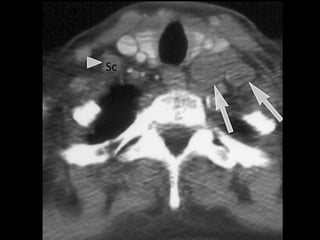

1. Highest mediastinal LNs

Upper border: lower border or cricoid.

Lower border: upper border of manubrium

and clavicles.

Medial border: medial edge of CCA.

Lateral boder: first rib.